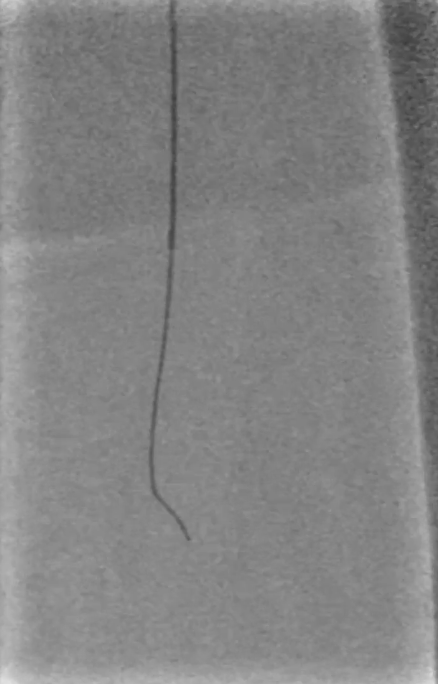

操作要点:在路径图引导下,使用超滑导丝配合6F导管选择进入支架近端(避免导丝从支架网眼穿出),随后采用新型超声开通导管尝试开通病变段。

器械优势:超声导管头端可发射超声波,能轻松通过坚硬闭塞部分;

注意事项:该导管硬度较大、方向选择性差,需配合V18导丝引导,推进时需缓慢操作并密切关注患者疼痛等不良反应。

调整与确认:开通至股浅动脉中段后,发现导丝向另一个方向打弯,退回后重新选择路径,最终顺利送至股浅动脉远端真腔,造影证实开通成功。